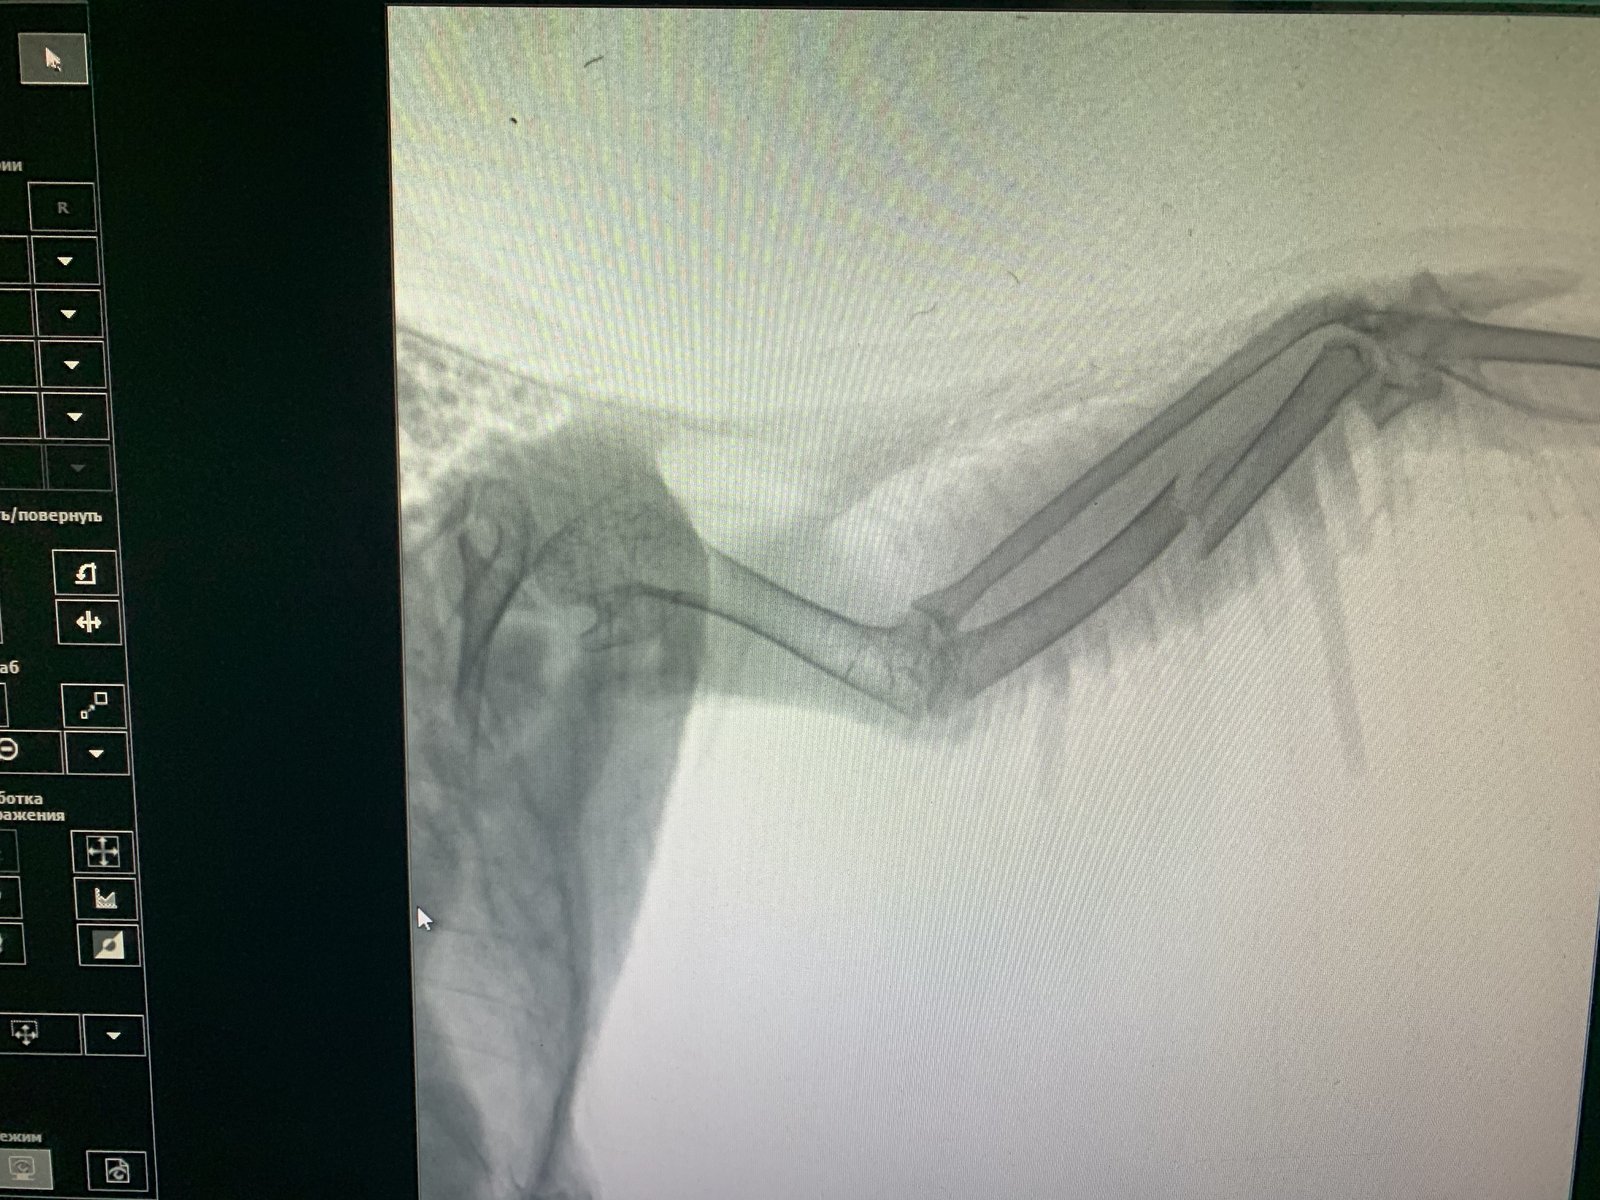

Ольга 0210 Опубликовано 16 октября, 2019 Автор #31 Опубликовано 16 октября, 2019 Здравствуйте!!!! Спасибо за участие!!!! По поводу первого врача - это был «чудо-доктор» Сергей, типа орнитолог, из ветклиники Паскаль, что на метро Водный Стадион, на ул. Смольная. Фамилию не запомнила, но орнитолог у них один. Все, что хочу сказать в его адрес - это только можно выразить русским матом.... по-другому не получится уже. Сегодня ездили к Zosia, в клинику на ул. Свободы, все выяснили-прояснили, оценили масштабы бедствия и наметили пути решения проблемы. Сделали рентгеновский снимок.... и вот пожалуйста, перелом крыла в двух местах со смещением кости налицо.... куда смотрел Сергей... сказать сложно. Zosia вначале перед рентгеном уже наощупь сказала, что перелом чувствуется. Все, что либо делать поздно, время упущено, шина бесполезна, поэтому ждёт, как срастется и принимаем обезболивающие (в нашем случае назначен Ибупрофен). Плюс Бисептол в суспензии, после Ибупрофена будем принимать Нимесулид. Лапка практически в порядке, а с крылом - полный покой в течение месяца и обезболиваем. Больше никаких отклонений и заболеваний за моим Филькой, так мы его назвали, замечено не было. Далее на повторный приём) Вот такие наши дела! Полная консультация по кормлению и уходу была дана мне сегодня, теперь буду ухаживать по -правильному)

Ольга 0210 Опубликовано 16 октября, 2019 Автор #32 Опубликовано 16 октября, 2019 Вот наш рентгеновский снимок!